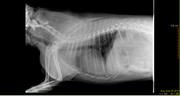

Коллапс трахеи форум